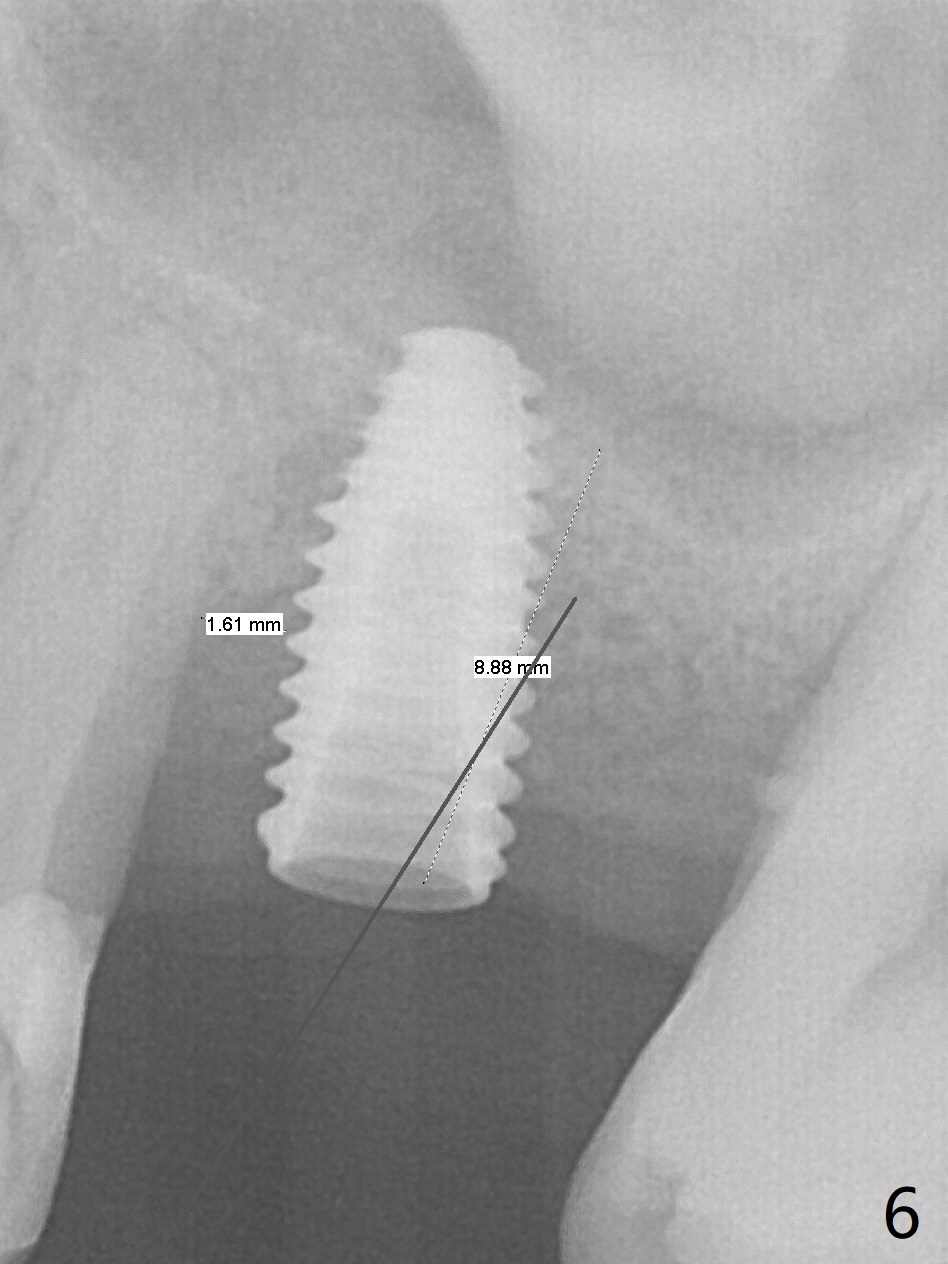

Trajectory of sinus lift without guide at #14 is off (Fig.1 (Magic Sinus Lifter (L) for 9 mm (gingival level)) and needs to be corrected (Fig.2 long line) by re-using 4.8 mm Magic Drill. Following placement of PRF membrane and Demineralized Cortical Allograft (.125-.850 mm) for sinus lift (Fig.3 black dashed line), a 4x10 mm dummy implant is placed with off trajectory. The latter will be fixed by using Lindmann bur to remove the bone distal (Fig.4). The result is less satisfactory with placement of 4.5x10 mm dummy implant (Fig.5). It appears necessary to initiate a new osteotomy (Fig.6 long black line). In fact the result is appealing (Fig.7). The final implant (5x7.3 mm) seems to be placed ideally shown by PA (Fig.8) and BW (Fig.9). Immediately postop CT demonstrates distal defect (Fig.10 *;3-D) and supracrestal placement palatal (Fig.11 P; coronal section). More allograft is then placed in these 2 areas. In all, it is difficult to establish a correct osteotomy without guide. The patient return for uncover 3.5 months postop, although there is a small hole in the middle of the incision (Fig.12). The crown/abutment becomes loose less than 1 month post cementation when the patient chews something tough. It is more related to the unfavorable implant/crown ratio. It is loose again 2 months later. Screw driver is buried inside the abutment with plumber tape. When it is loose for the 3rd time 13 months post cementation, the existing screw driver with a created slot (for retention) is buried without plumber tape after retorque at 35 Ncm (Fig.13). A tissue-level implant should have been used.